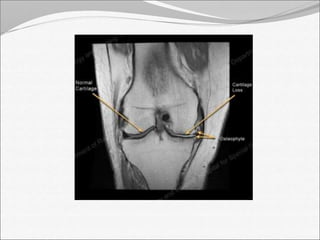

Joint space

decreased

osteophytes AP view

• 15.

Joint space decreased osteophytes AP view